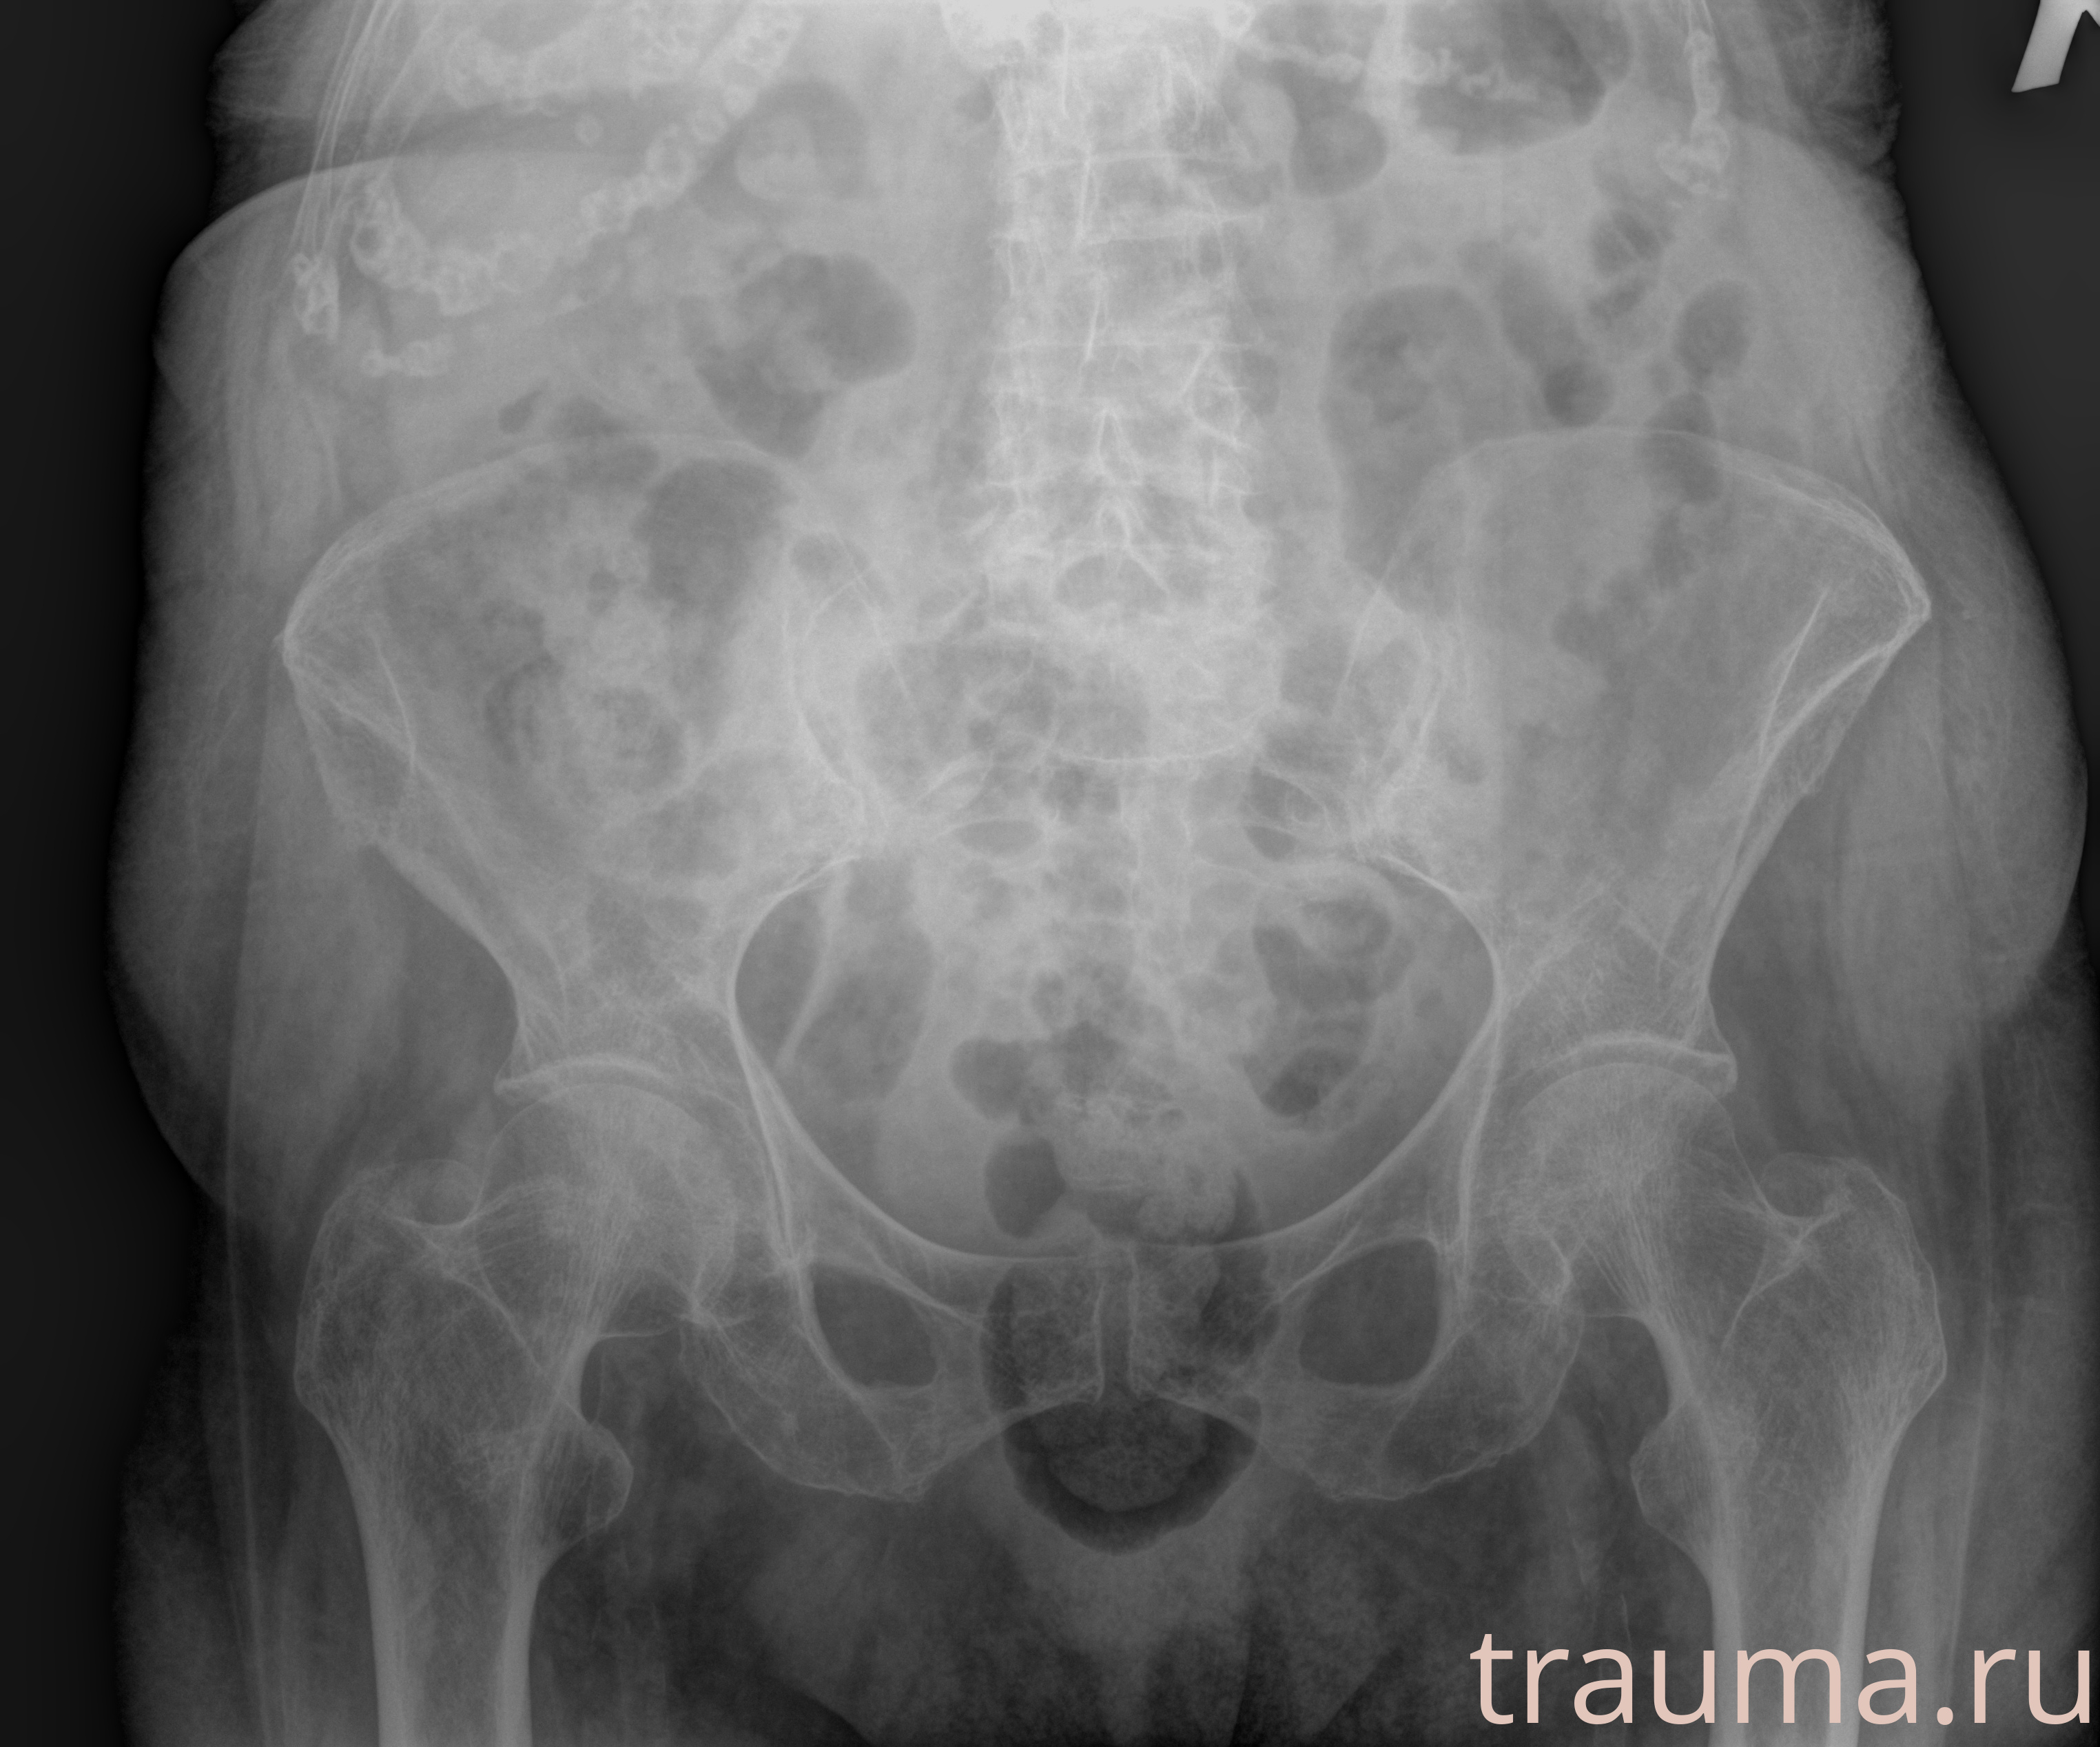

Рентгенограммы

Рентген на дому: по вашему адресу приезжает врач-рентгенолог, травматолог-ортопед с мобильным рентгеновским аппаратом, проводит диагностику травмы или заболевания, делает необходимые рентгенограммы, дает рекомендации по дальнейшему лечению. Получить качественные снимки в домашних условиях возможно благодаря уникальной методике, разработанной МосРентген Центром для института  Склифосовского